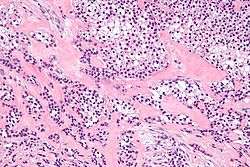

| Micrograph of a hyalinizing clear cell carcinoma showing the characteristic clear cells and surrounding hyalinized stroma. H&E stain. | |

HCCC consist of cells with abundant clear cytoplasm, arranged in cords, trabeculae or clusters in a hyalinized stroma.[4] Nuclear pleomorphism is usually minimal and mitoses are infrequently seen.[2]

Owing to their glycogen content, which explains the "clear" appearance under the microscope, tumour cells stain with PAS. Immunostains for S100 and smooth muscle actin (SMA) are typically negative, but positive for cytokeratins and epithelial membrane antigen (EMA).